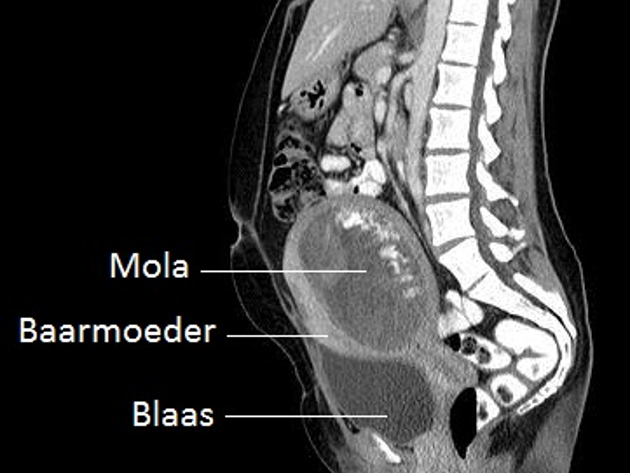

Hiernaast ziet u een voorbeeld van een CT-scan die een mola-zwangerschap laat zien.

Onderzoek richt zich op het opsporen van uitzaaiingen (metastasen) buiten de baarmoeder. Het vinden van uitzaaiingen is van belang voor het starten van de goede behandeling. Voor de nacontrole is beeldvorming van de uitzaaiingen echter van minder grote betekenis omdat deze, met name in de longen en hersenen, nog lang na het verdwijnen van actieve trofoblastcellen, zichtbare afwijkingen kunnen geven zonder dat er actieve tumor is. Bij alle patiënten met GTN wordt een longfoto gemaakt, eventueel een CT-scan van de borstkas/borstholte, bekken en buik om een risico indeling te kunnen maken. Een MRI van de hersenen is alleen nodig bij aanwezigheid van longmetastasen en bij hoog-risico patiënten.

De afkorting CT staat voor 'Computer Tomogram'. De CT-scanner werkt met dezelfde röntgenstralen als bij een 'gewone' röntgenfoto.Alleen maakt de CT-scanner dwarsdoorsneden van het lichaam, waardoor de arts als het ware plakjes van het lichaam kan zien. Als alle gefotografeerde plakjes achter elkaar worden gelegd, ontstaat een driedimensionaal beeld.